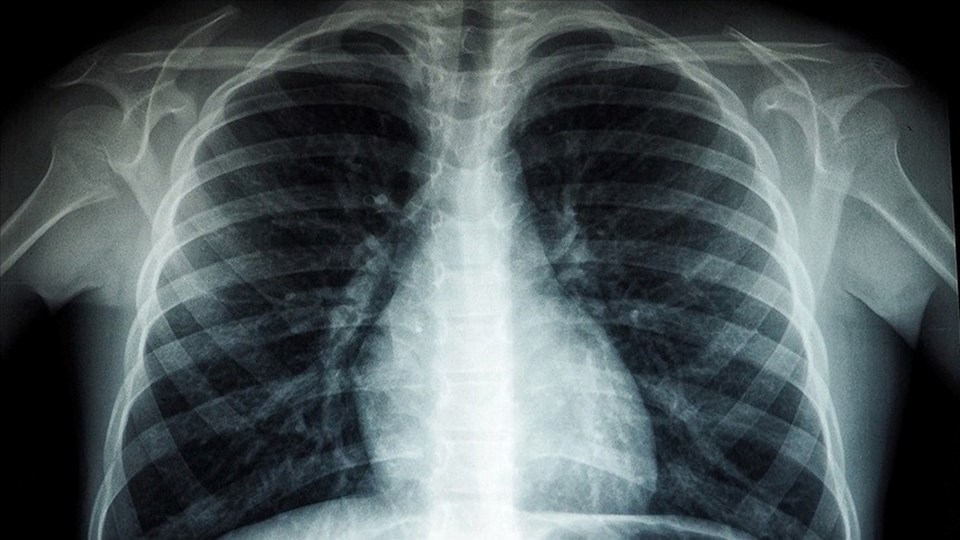

Verem hastalığı, yani tıbbi adıyla tüberküloz (TB) hava yoluyla bir bireyden diğerine yayılan, bulaşıcı bir akciğer hastalığıdır. Verem hastalığı Mycobacterium Tuberculosis isimli bakterilerden kaynaklanır. Verem hastalığı tedavi edilebilir ve verem aşısı ile önlenebilir bir hastalıktır.

Verem hastalığı yani akciğer tüberkülozu havaya salınan mikroskobik damlacıklar yoluyla insandan insana yayılan bakterilerden kaynaklanır.